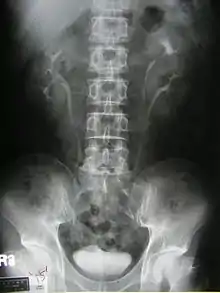

Duplicated ureter or duplex collecting system is a congenital condition in which the ureteric bud, the embryological origin of the ureter, splits (or arises twice), resulting in two ureters draining a single kidney. It is the most common renal abnormality, occurring in approximately 1% of the population.[1][2]

Diagnosis

Prenatally diagnosed hydronephrosis (fluid-filled kidneys) suggest post-natal follow-up examination. The strongest neo-natal presentation is urinary tract infection. A hydronephrotic kidney may present as a palpable abdominal mass in the newborn, and may suggest an ectopic ureter or ureterocele. In older children, ureteral duplication may present as: